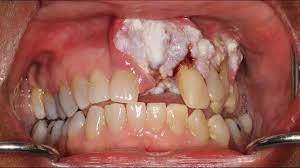

Tanda amaran awal kanser mulut termasuk luka mulut, tompok putih atau merah, dan kelembutan atau kesakitan. Kanser mulut adalah salah satu jenis kanser yang kurang diketahui umum. Rawatan kanser mulut adalah sama seperti rawatan kanser yang lain iaitu ia bergantung dengan tahapan kanser pesakit pembedahan jika kanser tersebut telah merebak ke kalenjar limfa, doktor juga perlu membuang kalenjar limfa tersebut. Mengunyah pinang dengan / tanpa tembakau; Kebanyakan orang penderita gejala awal kanker mulut mungkin akan berpikir bahwa lidah yang sakit hanyalah gejala sariawan biasa mungkin sehingga diabaikan. Ulser mulut petanda awal kanser. Pada awalnya tentu ada luka (merujuk pada keadaan tisu yang abnormal pada tubuh) awal kanser. Tanda dan gejala kanser mulut ulser mulut atau luka yang tidak sembuh bengkak yang berterusan selama lebih dari 3 minggu benjolan atau penebalan kulit atau lapisan mulut sakit ketika menelan gigi longgar tanpa sebab yang jelas sakit rahang atau kekakuan sakit tekak suatu rasa ada sesuatu yang. Sebab tu perlukan pemeriksaan doktor. Jika ada tanda tanda ni segeralah dapatkan pemeriksaan doktor sebab kalaupun ada tanda tanda ni tak semestinya kanser & tak semestinya bukan kanser jugak. Didalam kanser mulut, tanda dan gejala boleh dibahagikan ke peringkat awal atau peringkat lanjut. Gejala adalah simptom yang dialami oleh penderita. Tompok putih (leukoplakia) tompok merah (erythroplakia) nafas berbau (halitosis) anda juga mungkin mengalami :

Kanser lisan juga boleh muncul sebagai patch putih atau merah pada gusi, tonsil, atau lapisan mulut.

Kanser lisan juga boleh muncul sebagai patch putih atau merah pada gusi, tonsil, atau lapisan mulut. Ulser mulut petanda awal kanser. Sebab tu perlukan pemeriksaan doktor. Satu lagi tanda kanker mulut awal yang harus segera diperiksakan adalah ketika timbul rasa sakit di bagian lidah. Tanda amaran awal kanser mulut termasuk luka mulut, tompok putih atau merah, dan kelembutan atau kesakitan. For more information and source, see on this link : V ulser yang lambat sembuh (melebihi 2 minggu). Kanser atau ketumbuhan luar kawal berlaku di dalam badan, perlukan rawatan segera bagi mengelak pelbagai komplikasi kesihatan hingga boleh meragut nyawa. Terdedah pada sinaran matahari secara berlebihan; Rawatan kanser mulut sehingga ke hari ini, rawatan untuk kanser mulut hanyalah pembedahan. Rawatan kanser mulut adalah sama seperti rawatan kanser yang lain iaitu ia bergantung dengan tahapan kanser pesakit pembedahan jika kanser tersebut telah merebak ke kalenjar limfa, doktor juga perlu membuang kalenjar limfa tersebut. Gejala adalah simptom yang dialami oleh penderita. Kkmalaysia on twitter 12 tanda tanda kanser mulut yang kita boleh buat pemeriksaan sendiri atau mse segera berjumpa doktor untuk pemeriksaan lanjut jika anda mempunyai tanda tanda ini kanser mulut boleh dirawat jika dikesan.